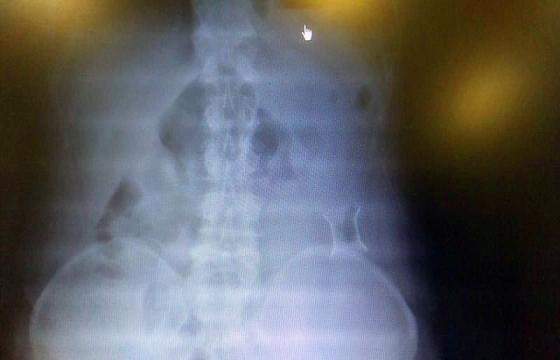

受試患者在結(jié)腸端端吻合術(shù)中,使用我司新研制產(chǎn)品達到了理想的預(yù)期效果。患者術(shù)后7天、14天X光片顯影,可降解腸道支架均能按研制設(shè)計的預(yù)期時間節(jié)點保持應(yīng)有強度,術(shù)后21天X光片顯示可降解腸道支架已完全破碎,并排出體外。在整個試驗過程中,病患無任何不良反映,耐受良好。